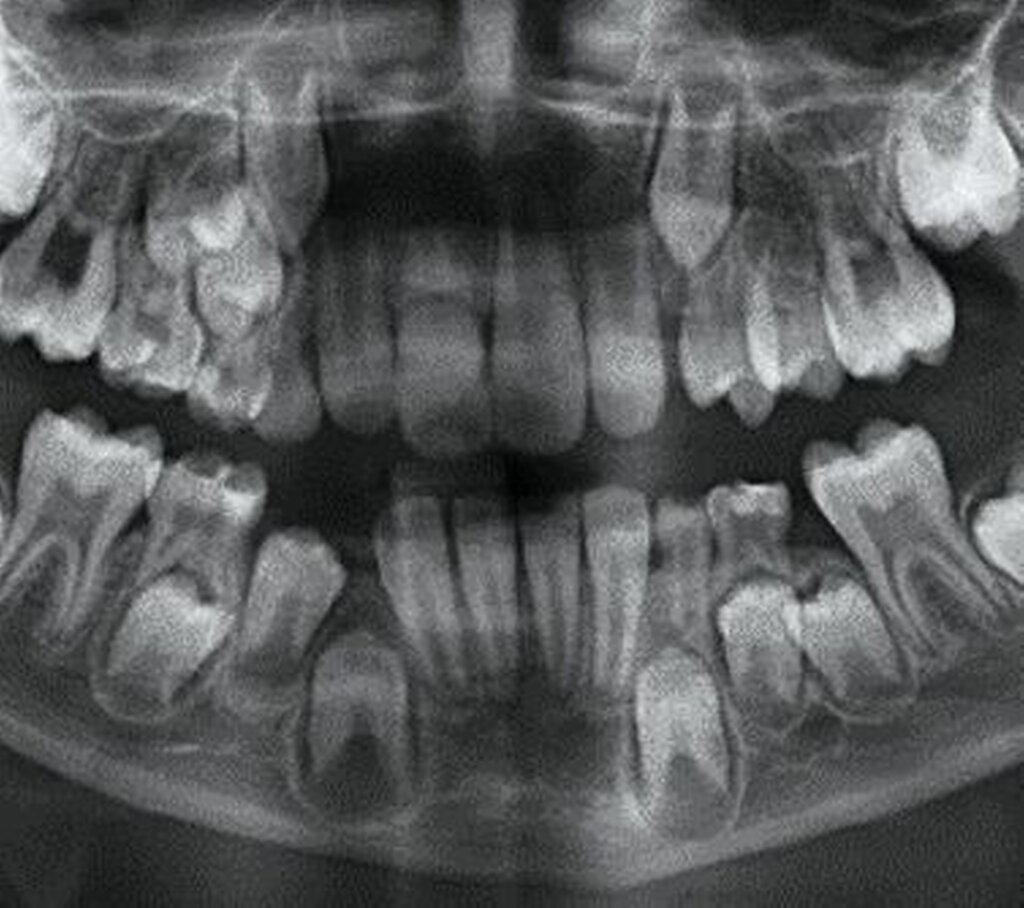

Dislokationsverletzungen von Zähnen können nicht selten mit einer Fraktur des zahntragenden Alveolarfortsatzes kombiniert sein, die auf Panoramaschichtaufnahmen oder gegebenenfalls weiterführenden Aufnahmen (Einzelzahnfilm, DVT) zur Darstellung kommen. Je nach Schweregrad wird hier zwischen einer partiellen Fraktur (Bruch der vestibulären oder oralen Alveolenwand) und einer vollständigen (Bruch der vestibulären und oralen Alveolenwand) im Sinne einer dislozierten beziehungsweise nicht dislozierten Fraktur des Alveolarfortsatzes unterschieden.

Klinisch findet sich neben häufigen, meist vertikalen Schleimhauteinrissen gegebenenfalls eine tastbare Stufenbildung (Abbildung 6). Dislozierte Alveolarfortsatzfrakturen gehen in der Regel mit einer Okklusionsstörung einher, die Sensibilität der betroffenen Zähne geht dabei häufig verloren. Die Therapie der Alveolarfortsatzfrakturen weist einige Besonderheiten auf, die in der entsprechenden Empfehlung der Leitlinie aufgeführt sind.